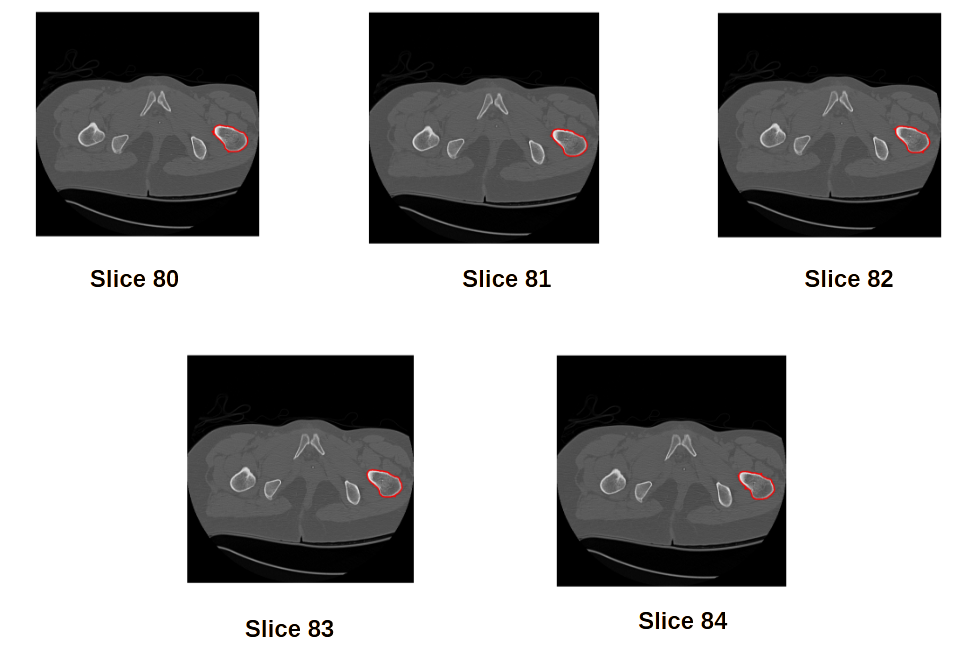

CT images assist the clinical practitioners to assesses the internal structure for deformity when met with serious injuries. CT images captures the intensity variations of different internal body parts like bones, muscles, fat, organs and blood vessels relative to the water in Hounsfield Unit [19]. The HU are mapped linearly to the gray scale range [0, 255]. CT Scanning captures human body in incremental scanning and provides up to 350 slices depending on the thickness of the slice or resolution of the CT scanning machine. The practicing clinicians needs to analyze each slice manually to precisely locate the deformity or injury in the internal structure. Manually analyzing slice-by-slice is a tedious task and the 3D structure need to be constructed in his imagination based on his learning and experience. Most important internal organ that will be assessed in all these CT slices is bone. Segmenting the bone in all these slices and reconstructing the 3D Structure will assist the clinicians in saving time and enough room for other medical procedures. Sample CT scan images [22] of pelvic bone from slice 80 to 84 with region of interest Pelvic bone femoral body is shown in Figure 2.

Refer to caption

Figure 2: CT Images Slices 80-84 with Region of Interest

After the traditional work flow, segmentation of the internal structure is performed on each slice of region of interest. To perform the task of image segmentation, each slice of CT Image is subjected to thresholding and followed by morphological operations, the boundaries of ROI are extracted. The results of segmentation on slice 80 to slice 84 are shown in Figure 3 for a threshold value above 400.

Figure 3: Contours of ROI